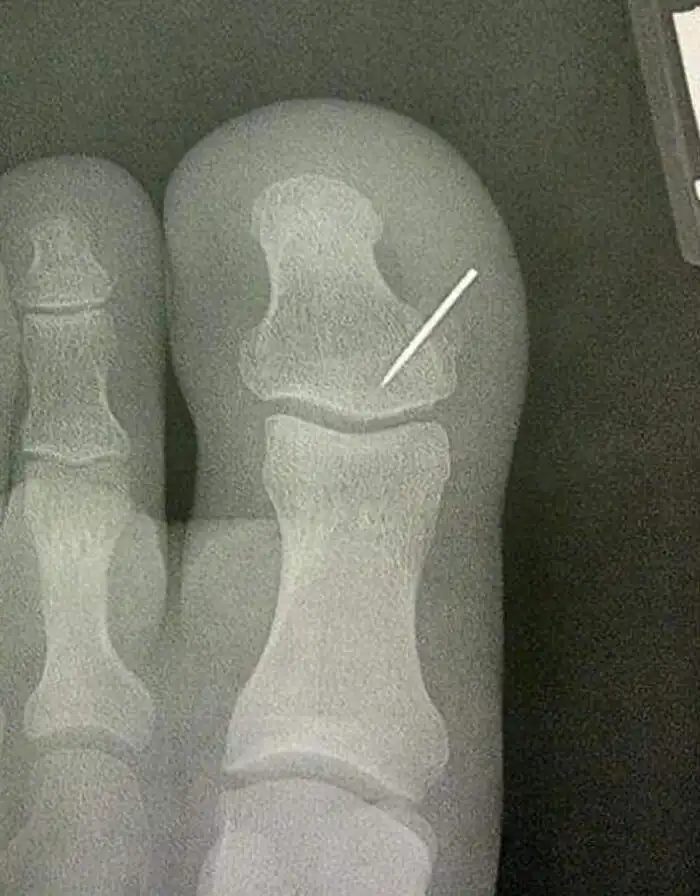

"Жена потеряла швейную иглу где-то на ковре. Через несколько дней я нашёл ее кусок"